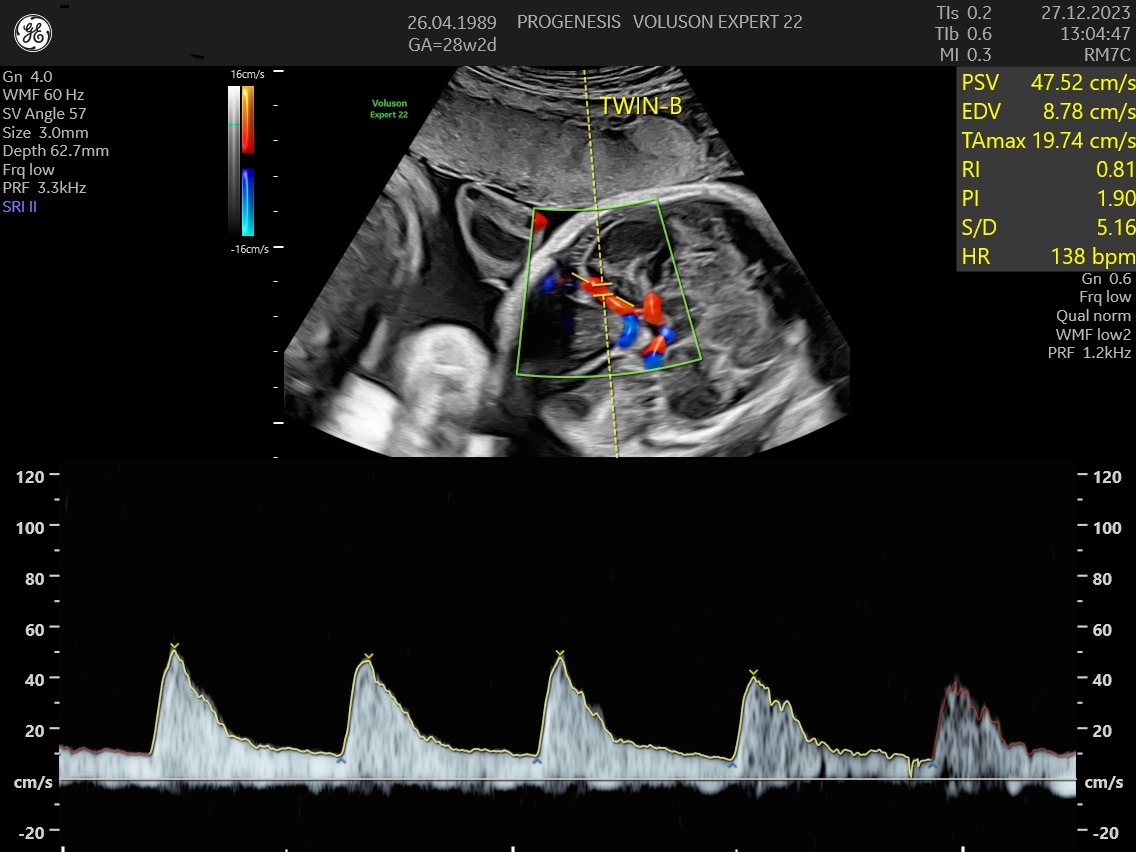

Ελέγχεται επίσης η παροχή οξυγόνου από της αρτηρίες της μητέρας στη μήτρα (Doppler μητριαίων αγγείων), από τον ομφάλιο λώρο στο έμβρυο (Doppler ομφαλικής αρτηρίας) καθώς και η ροή στην κεντρική αρτηρία του εγκεφάλου.